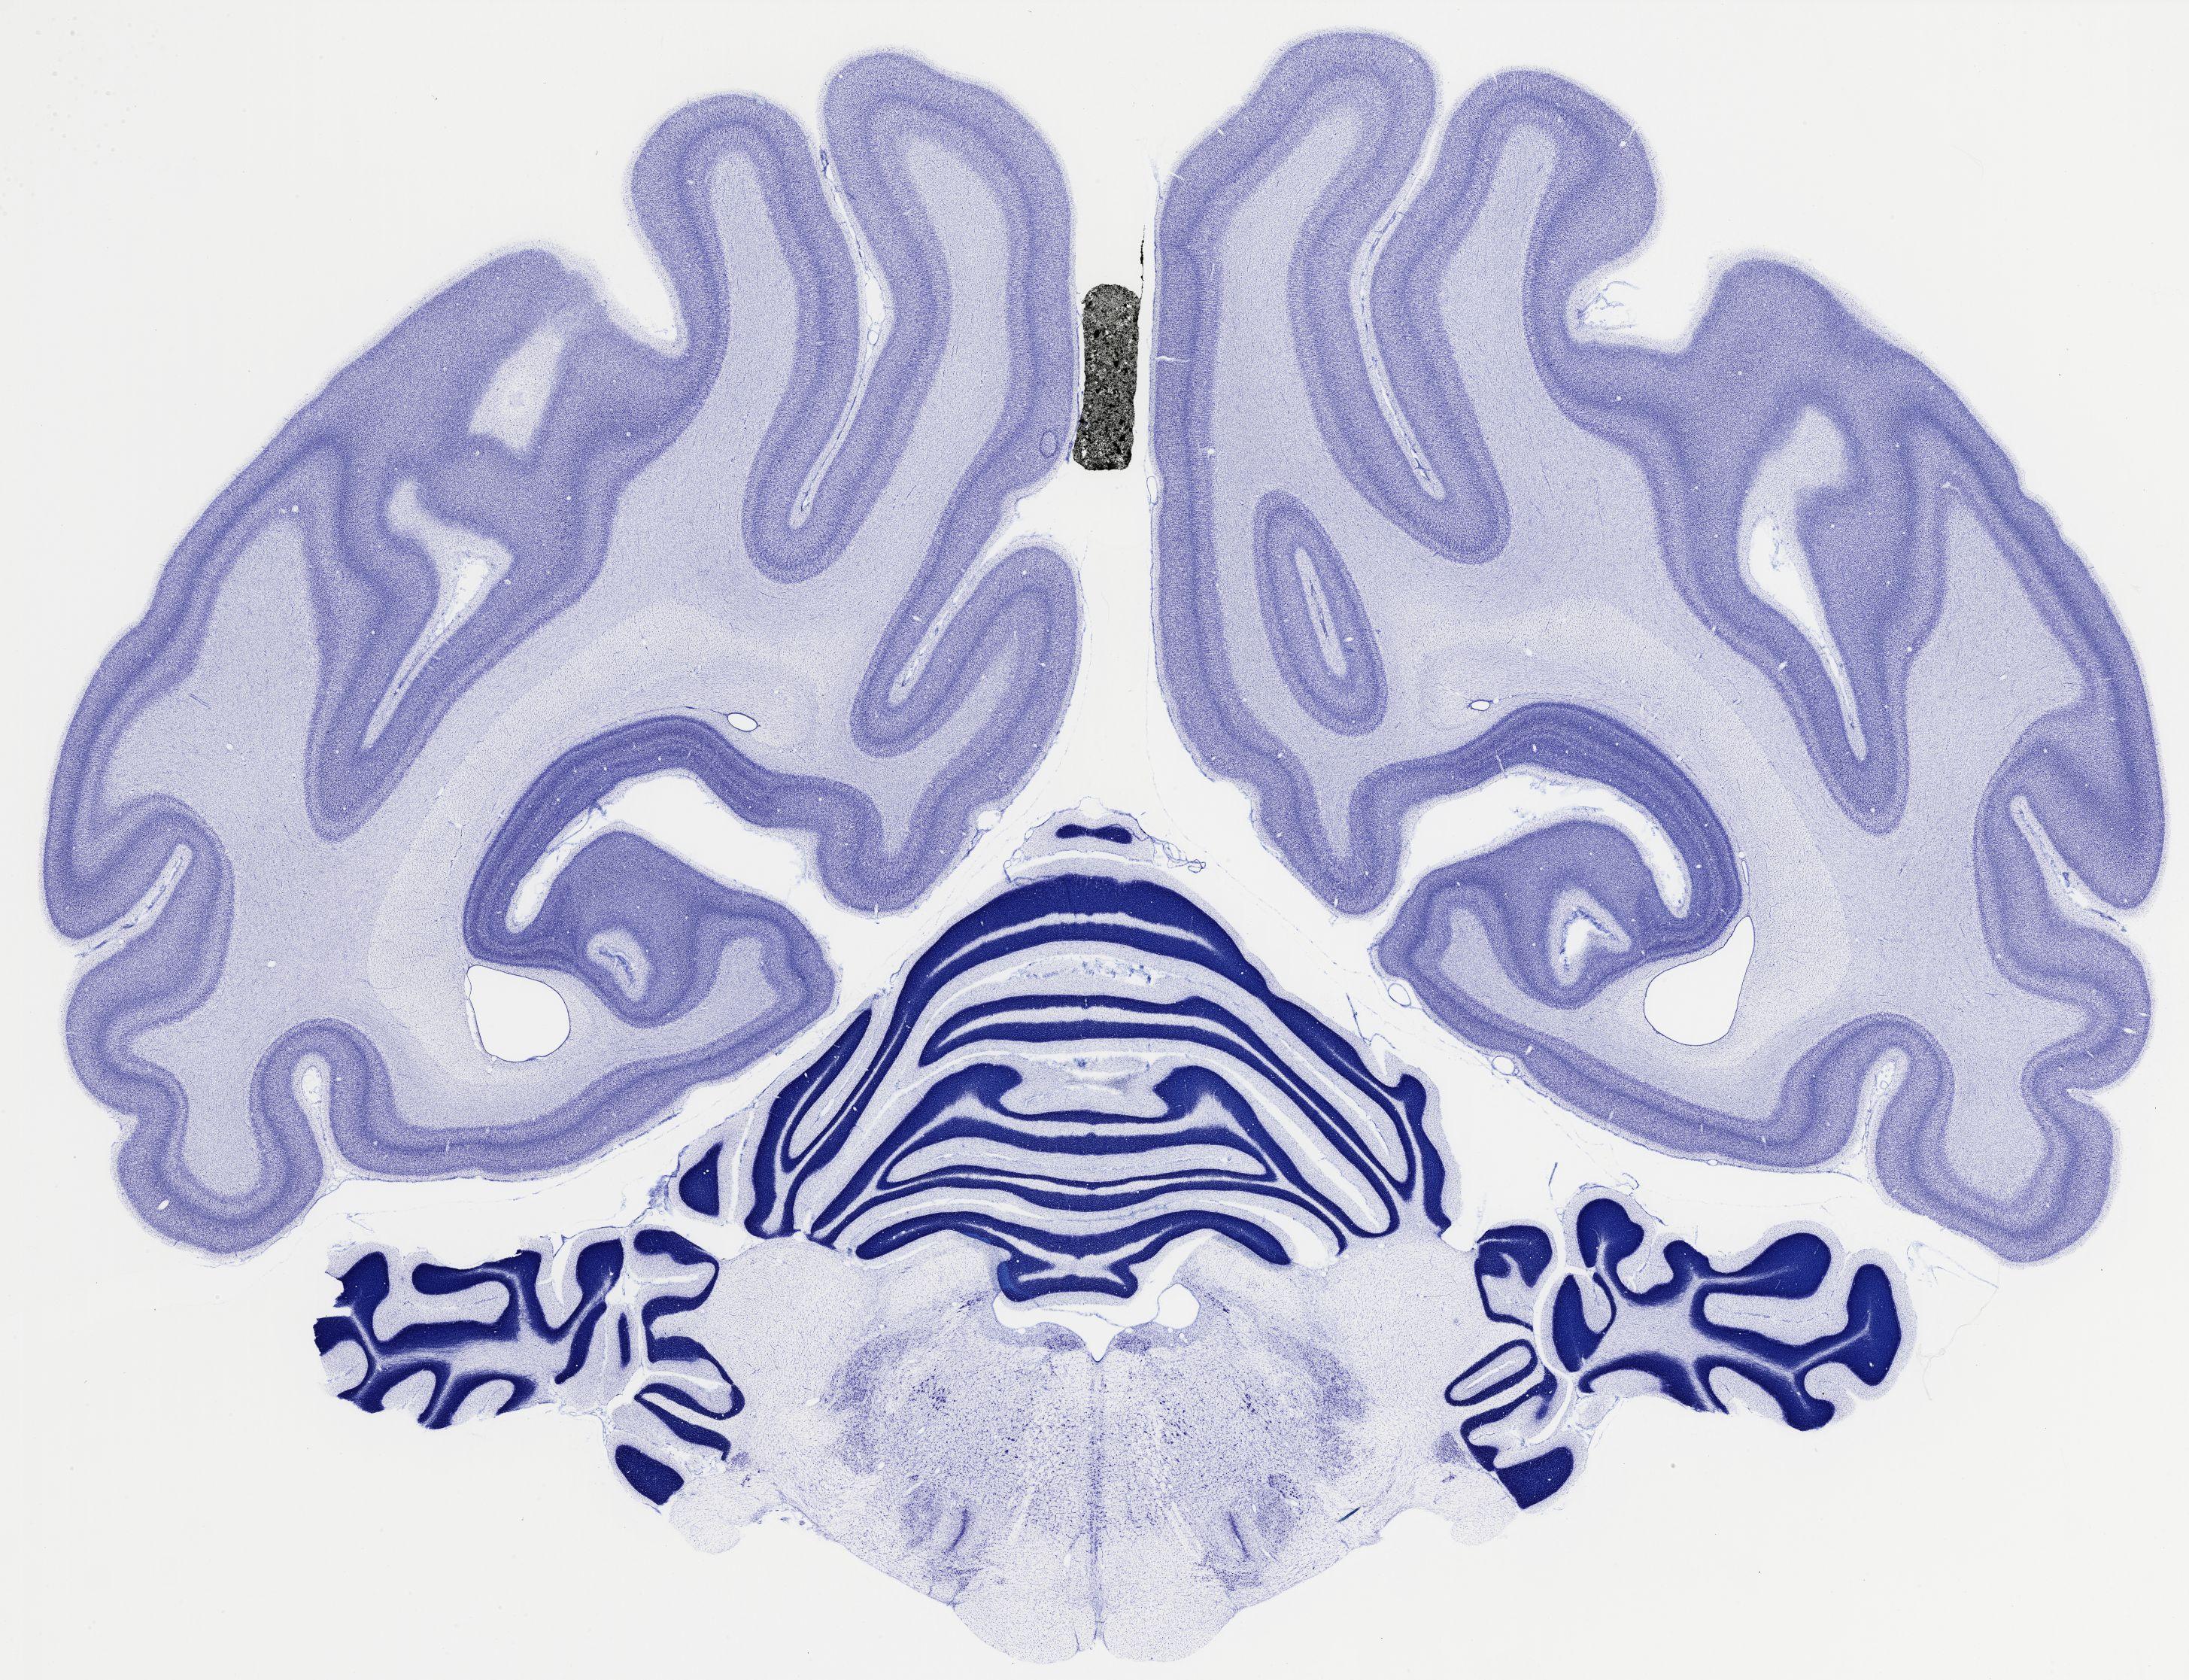

thumbnail

522